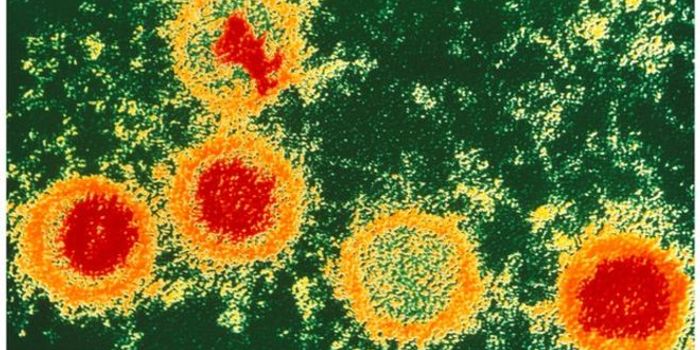

AUG 28, 2015MicrobiologyAs of 2012, roughly 35 million people were living with HIV worldwide, and 1.5 million died from AIDS-related illnesses i ...

SEP 30, 2015ImmunologyCurrently in the United States, 13 percent of the 1.2 million people infected with HIV are unaware of their condition (A ...